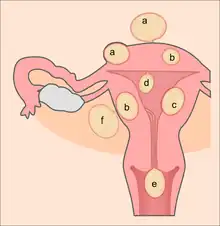

Location and classification

Growth and location are the main factors that determine if a fibroid leads to symptoms and problems.[7] A small lesion can be symptomatic if located within the uterine cavity while a large lesion on the outside of the uterus may go unnoticed. Different locations are classified as follows:

- Intramural fibroids are located within the muscular wall of the uterus. Unless they are large, they may be asymptomatic. Intramural fibroids begin as small nodules in the muscular wall of the uterus. With time, intramural fibroids may expand inwards, causing distortion and elongation of the uterine cavity.

- Subserosal fibroids are located on the surface of the uterus. They can also grow outward from the surface and remain attached by a small piece of tissue and then are called pedunculated fibroids.[1]

- Submucosal fibroids are most common type, located in the muscle beneath the endometrium of the uterus and distort the uterine cavity; even small lesions in this location may lead to bleeding and infertility. A pedunculated lesion within the cavity is termed an intracavitary fibroid and can be passed through the cervix.

- Cervical fibroids are located in the wall of the cervix (neck of the uterus). Rarely, fibroids are found in the supporting structures (round ligament, broad ligament, or uterosacral ligament) of the uterus that also contain smooth muscle tissue.

Fibroids may be single or multiple. Most fibroids start in the muscular wall of the uterus. With further growth, some lesions may develop towards the outside of the uterus or towards the internal cavity. Secondary changes that may develop within fibroids are hemorrhage, necrosis, calcification, and cystic changes. They tend to calcify after menopause.[33]